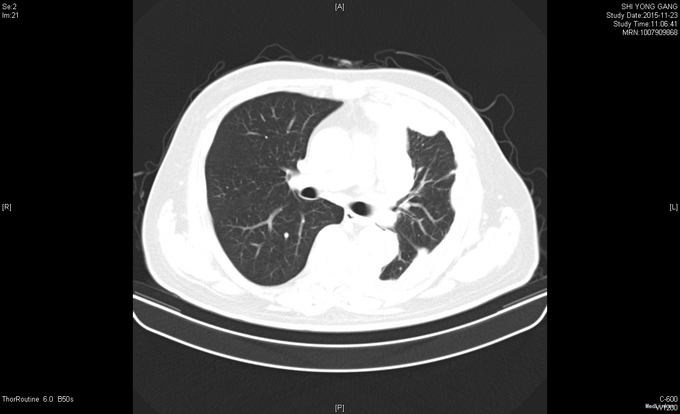

患者于2015年2月中旬无明显诱因出现咳嗽咳痰,中等量白色粘痰,无痰中带血,至当地卫生院予以消炎治疗(具体不详),症状无明显好转。出现胸闷气喘,平卧时加重,无粉红色泡沫痰,无发热,无咯血,至XX医院就诊,查胸部X线提示左侧大量胸腔积液。胸部及上腹部增强CT提示左肺上叶条索灶,左侧胸膜明显不均匀增厚,间皮瘤?转移?左侧胸腔积液,左下肺膨胀不全,肝右叶后段小类圆形稍低密度影,囊肿?胆囊壁增厚。右肾囊肿。腹膜后小淋巴结。2015-03-17 B超引导下行胸膜活检术,术后病理示(左侧胸膜穿刺)镜下见少量异型细胞,免疫组化结果:CK7(++),NapsinA(-),TTF-1(-),CK20(-),Villin(-),Ki-67(<2%+),CK(+),MC(+),结合HE切片、临床表现及影像学资料,符合恶性间皮瘤。头颅MRI未见异常。ECT全身骨显像未见异常。患者拒绝化疗等治疗后出院。后患者症状持续存在,遂于2015-07-21至XX医院就诊,排除禁忌,于2015-07-22予以化疗(培美曲塞二钠1g d1+顺铂40mg d1-3)1周期。并于2015年8月开始间断予以DC+CIK细胞免疫治疗。

查体:左下肺呼吸音低,余查体未见明显异常。 辅查:血常规、血生化等未见明显异常;肿瘤标志物:CA125 846.80IU/ml↑、CA15-3 101.60IU/mL↑、细胞角蛋白19片段(Cyfra21-1)5.25ng/ml↑ 胸部CT示:1、左侧胸膜间皮瘤治疗后,局部心包受侵可能,心包少量积液;2、左肺高密度灶,炎症可能,淋巴管转移待排;3、左侧胸腔少量积液左肺膨胀不全;4、纵隔多发稍增大淋巴结。腹部CT示:1、腹膜后多发稍大淋巴结;2、脾脏肿大;3、右肾多发囊肿;4、左侧胸膜不规则增厚,恶性病变可能,请结合临床;心包少量积液。头颅MRI、骨骼ECT未见明显异常。